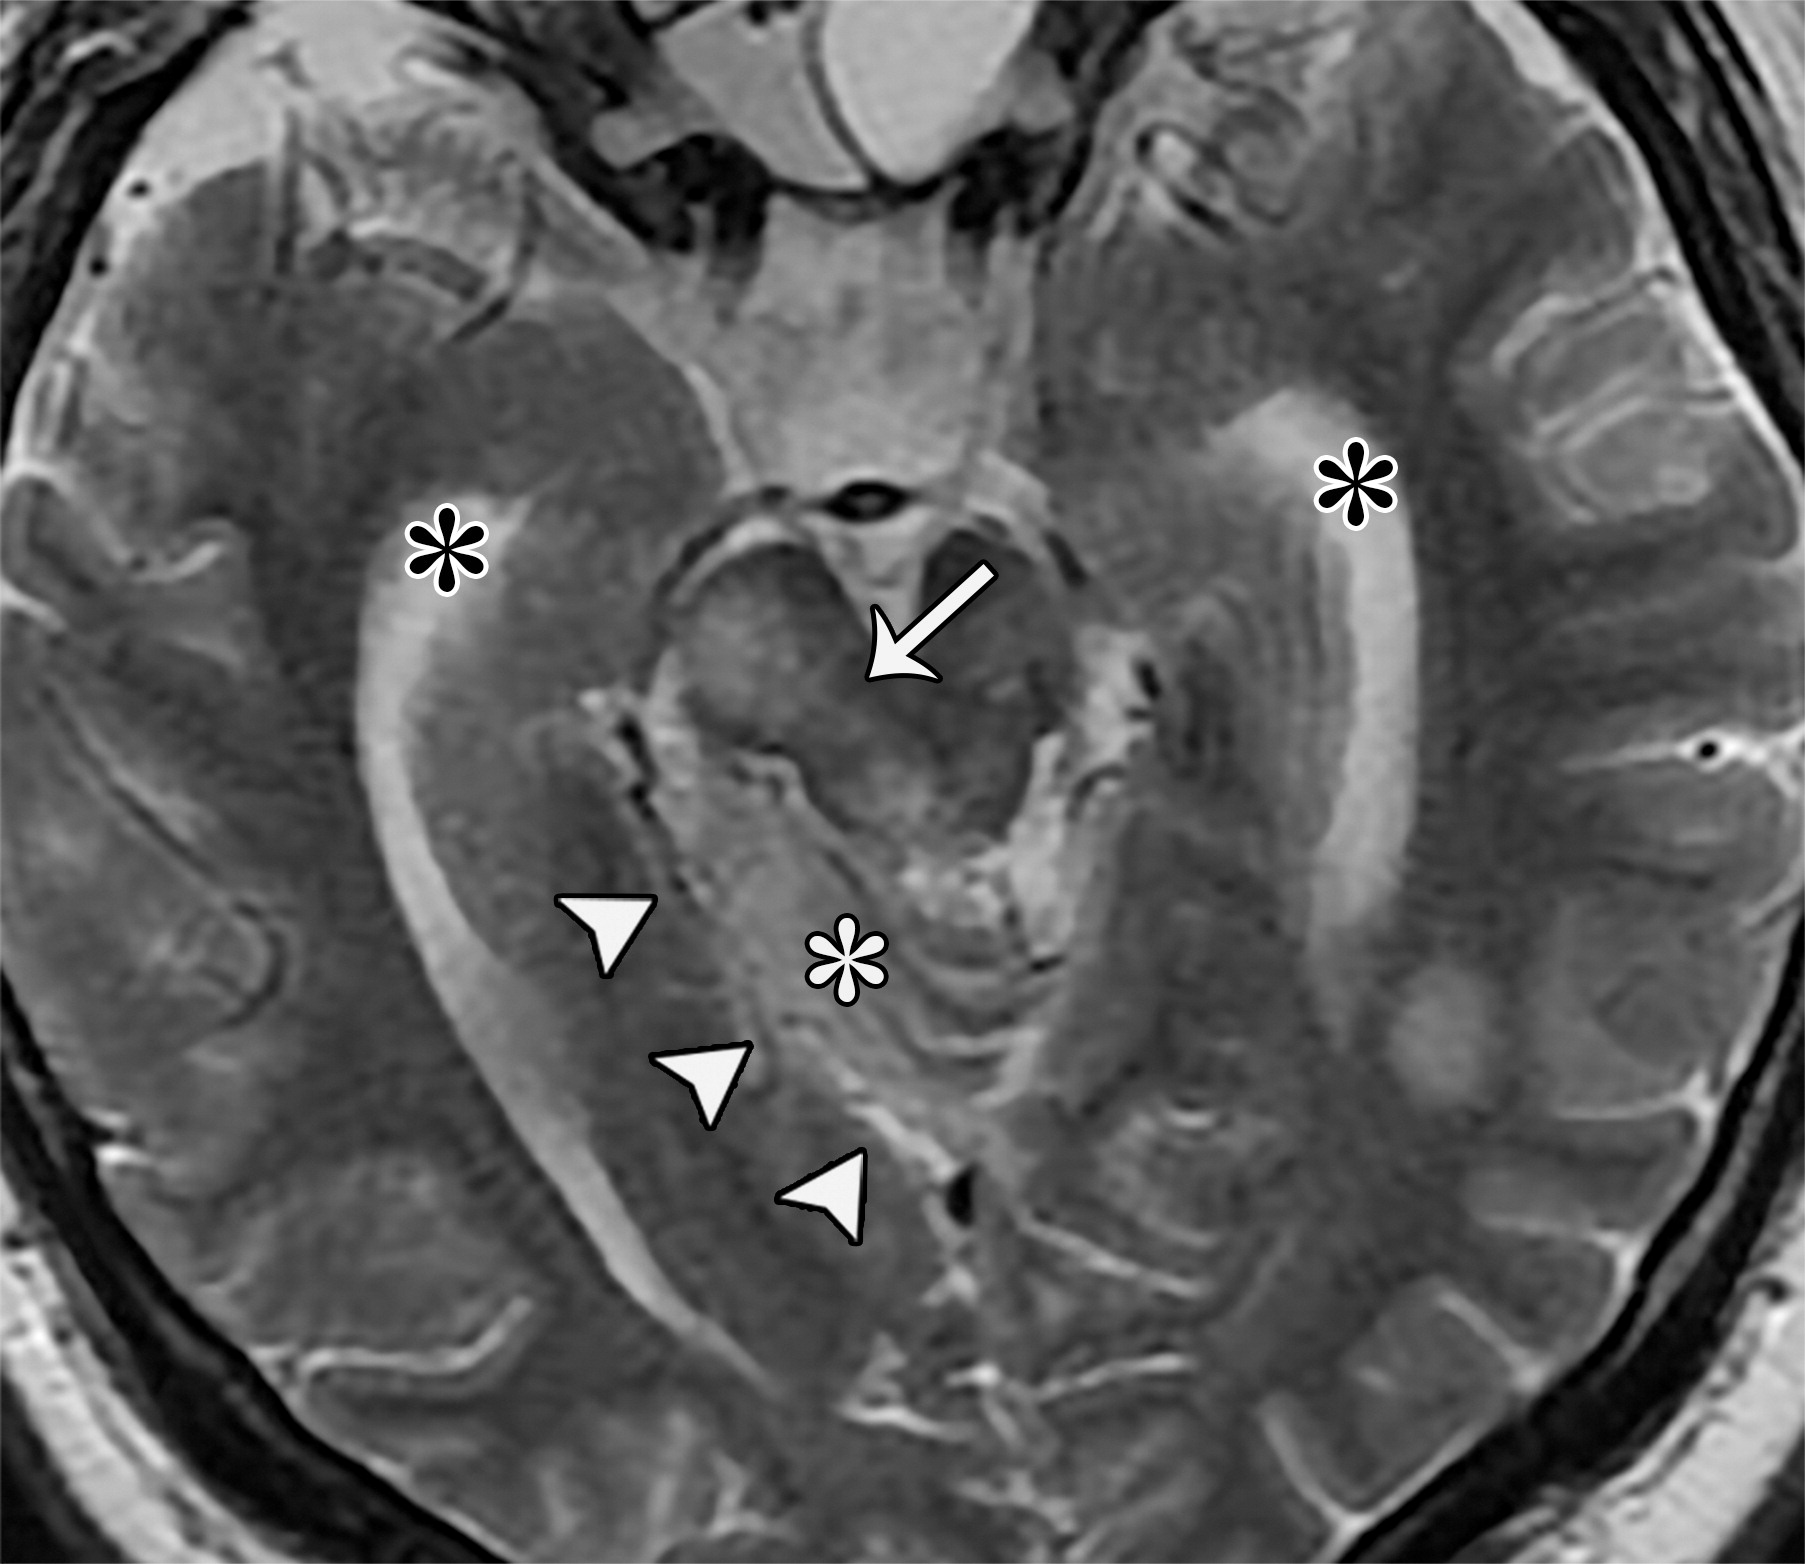

上升性小脑幕裂孔疝。26岁男性,切除髓母细胞瘤后。四叠体池,小脑上池,大脑脚间池的闭塞。下丘(白色短箭头)折叠于上丘的下方,且上丘及下丘两个结构均向上移位。脑干向前移位,导致脑桥池及延髓池间隙变窄(白色弯曲箭头),注意第三脑室顶的向上移位(白色长箭头),乳头体及灰结节向前移位并与中脑紧密相连(白色圆圈)。

4ba8451213c1f99e2e61ef93acd5cfd9.jpeg上升性小脑幕裂孔疝,33岁男性,可疑患有颅内病变。小脑组织(白色*)通过右侧小脑幕切迹(白色短箭头)向上疝出,导致右侧中脑周围池及左侧大脑脚池的闭塞,四叠体池间隙变窄,侧脑室颞角的扩张(黑色*),顶盖及右侧大脑脚(白色长箭头)的水肿。